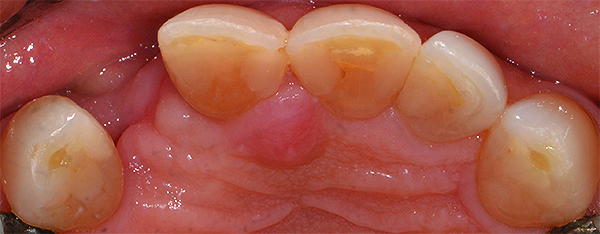

Based on the virtual plan, the treatment is carried out. An example of virtually planned and executed treatment is shown in Figure 2 through Figure 7. The patient presented with a missing maxillary right lateral incisor (Figure 2). Based on the patient’s desires, expectations, and comprehensive examination, a lithium disilicate fixed dental prosthesis (FDP) was planned to restore the missing lateral incisor. A virtual mock-up of the desired treatment plan was performed to delineate tooth length, width, and emergence profile (Figure 3). The treatment plan was then executed by preparing the abutment teeth to receive the FDP (Figure 4). An optical impression was made of the preparations and opposing teeth, and the resulting scans were virtually articulated (Figure 5). The optical impression was used to evaluate all aspects of the preparation, including finish line width and finish, path of insertion, and occlusal and axial reduction. It was also examined for the presence of undercuts, which were delineated by a red color (Figure 6). Errors in preparation design can be easily corrected and a new optical impression of the modified areas can be made without having the patient return for another visit. Once completed, the digital files can be sent to the laboratory for restoration design and manufacture, or used to design and fabricate the restoration using an in-house milling machine.14 An example of a completed restoration is shown in Figure 7.

(2.) A patient presented with a missing lateral incisor. The patient was treatment planned to receive a fixed dental prosthesis retained by the adjacent central incisor and canine.

Figure 2